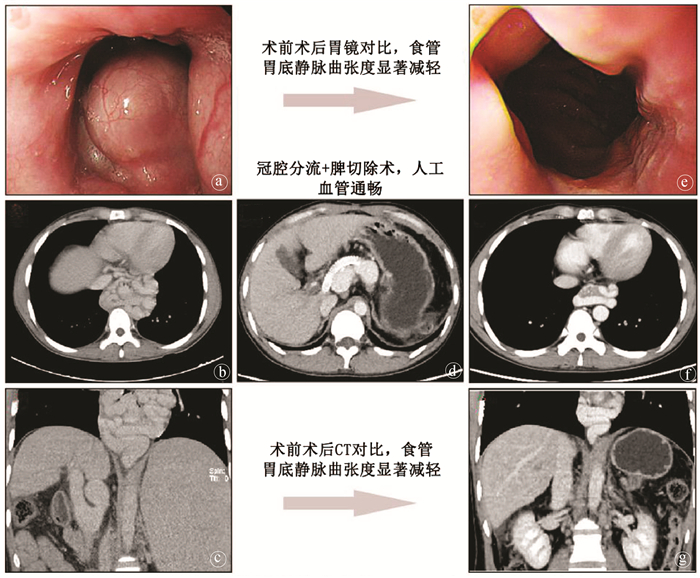

Value of coronary-caval shunt combined with splenectomy in portal hypertension

Weijie WANG, Rongtao ZHU, Ruopeng LIANG, Jian LI, Chixian ZHANG, Dexu LI

2021, 37(4): 898-901. DOI: 10.3969/j.issn.1001-5256.2021.04.034

Abstract(813) HTML (217) PDF (4530KB)(40)